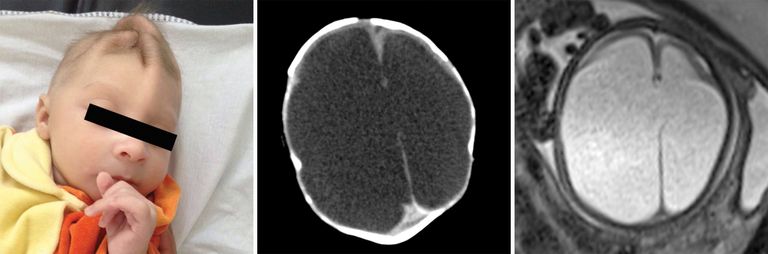

وقالت الصحيفة، إن دراسة صور الأشعة على المخ، وصور الموجات فوق الصوتية لـ 45 طفلًا برازيليًّا أصيبت أمهاتهم بالفيروس خلال فترة الحمل تبين أنه يمكن أن يلحق أضرارًا جسيمة بعدة أجزاء مختلفة من مخ الجنين أكثر من مجرد تشوه الرأس، وهي حالة صغر الرأس غير المعتادة التي أصبحت بمثابة العلامة الخبيثة لـ"زيكا".

وأوضحت أن الصور التي نشرت، أمس الثلاثاء، في دورية "علم الأشعة"، تشير أيضًا إلى احتمال خطير؛ لأن بعض الأضرار تحدث في مناطق الدماغ التي لا تزال في طور النمو بعد الولادة، وربما يواجه الأطفال الذين يولدون بدون تشوه واضح مشكلات عندما يكبرون.

ويقول الخبراء، إن معظم الأطفال الذين شملتهم الدراسة ولدوا بتشوه الرأس، على الرغم من أن 3 لم يصابوا به، وكل منهم عانى تشوهات أخرى أيضًا، تظهر كلها تقريباً قبل صغر الرأس لأنه في الحقيقة نتيجة فشل الدماغ في النمو بشكل كامل أو تعرضه لأضرار على نحو مستمر.

من جانبها قالت الطبيبة ديبورا ليفين، وهي مؤلفة الدراسة وأستاذة الأشعة في كلية الطب بجامعة هارفارد، إن "المخ الذي ينبغي أن يكون هناك ليس هناك، والتشوهات التي نراها في الدماغ تشير إلى اختلال في عملية نمو المخ في وقت مبكر للغاية".

وتظهر صور الأشعة أن أهداف "زيكا" في المخ، التي يعرف بعضها الخبراء، تشمل "الجسم الثنفي" وهو الجزء الذي يسهل التواصل بين شطري الدماغ، والمخيخ الذي يلعب دورًا هامًّا في الحركة والتوازن والكلام؛ والعقد العصبية القاعدية التي تشارك في التفكير والعاطفة.